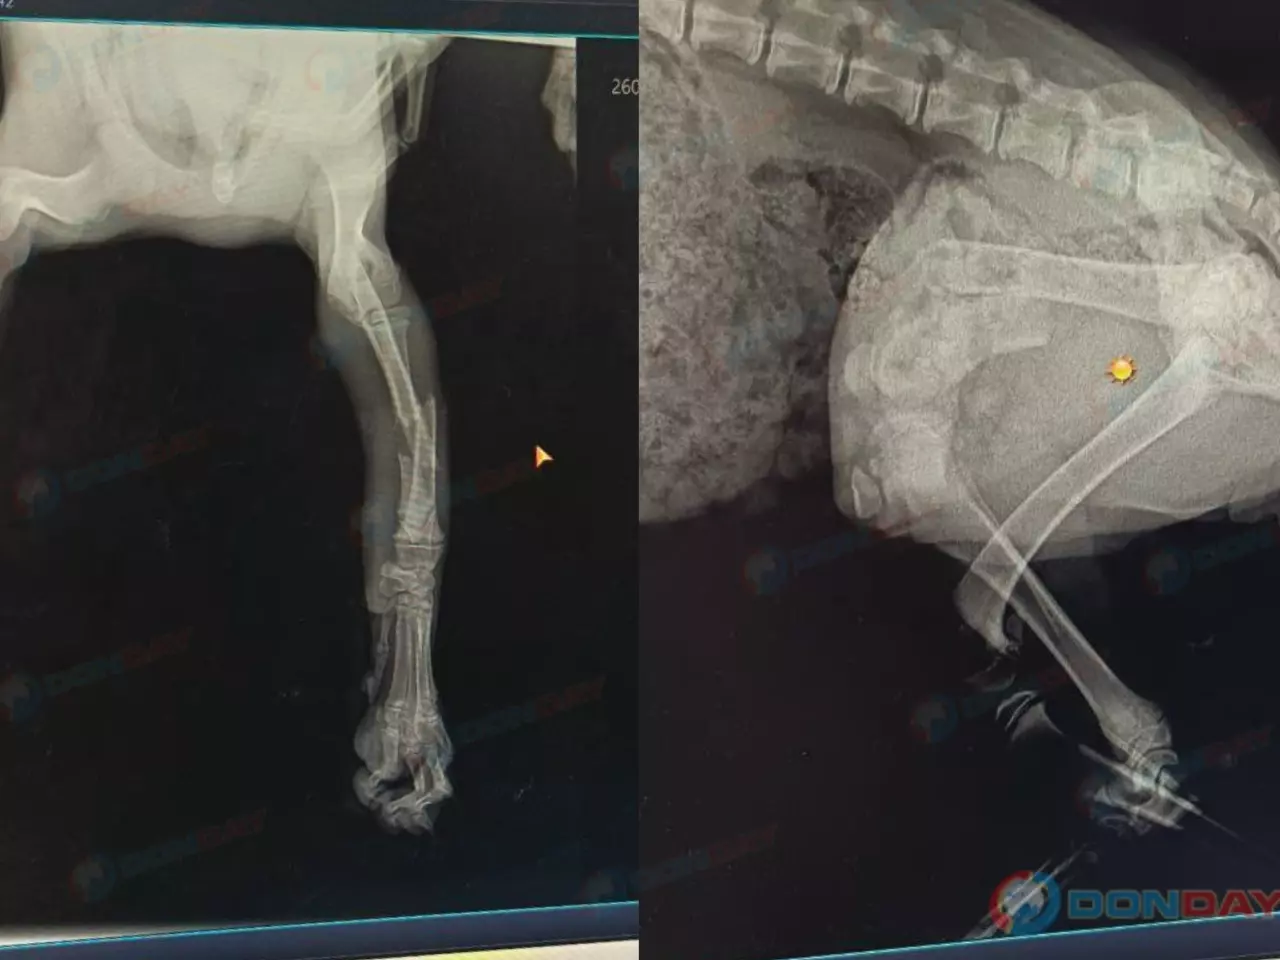

У трехмесячного малыша диагностировали переломы двух лап со смещениями. Крошечное существо, полное страха и боли, нуждалось в спасении. Требовалась срочная операция — и снова на помощь пришли добрые сердца. За короткое время неравнодушные жители Зверево собрали 25 000 рублей.

Хирурги сделали все возможное: в переднюю лапку Бусе вживили спицу, а в бедро задней — специальную пластину. Каждая минута операции казалась вечностью для тех, кто переживал за судьбу щенка.